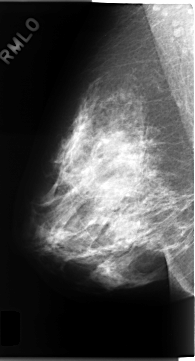

C_0150_1.RIGHT_MLO

RIGHT_MLO LINES 4688 PIXELS_PER_LINE 2528 BITS_PER_PIXEL 12 RESOLUTION 50 NON_OVERLAY